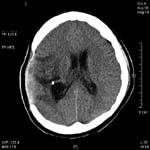

<ÇãÇ÷¼º

³úÁ¹Áß>

ÁÂÃø

Áß³úµ¿¸ÆÀÇ Æó»öÀ¸·Î ÀÎÇÑ ³ú°æ»ö¼Ò°ß(Ç÷°üÁ¶¿µ¼ú»ó

Áß³úµ¿¸ÆÀÌ º¸ÀÌÁö ¾Ê°í ÀÖ´Ù)